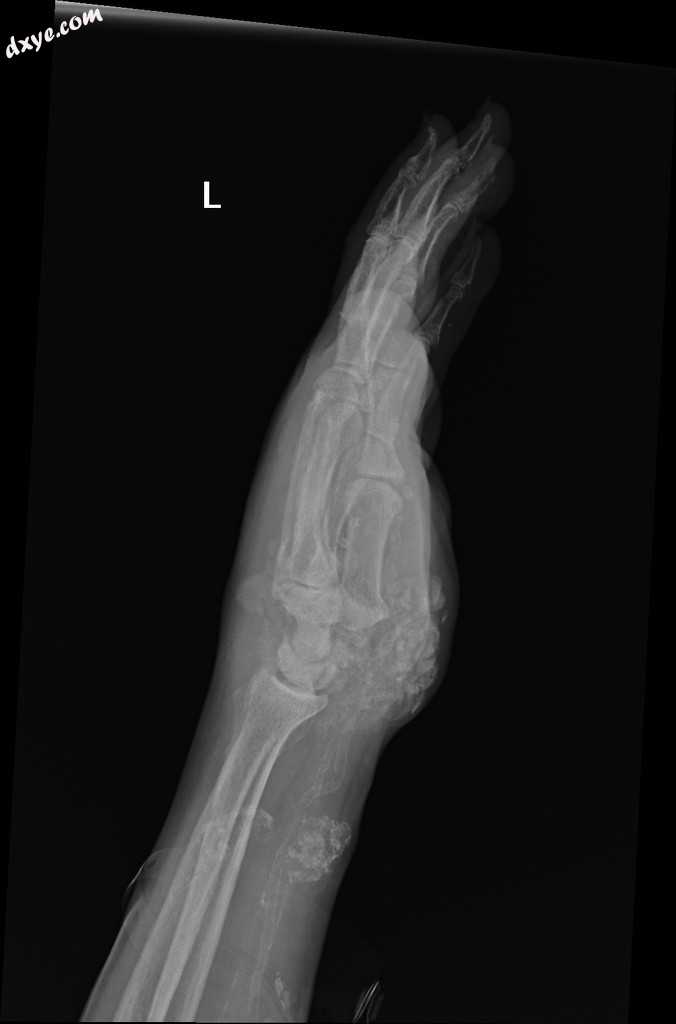

X射线

3.jpeg

正位

4.jpeg

侧位

在两个腕关节周围和左前臂远端可见大量软组织钙化,上覆软组织肿胀。

可见的骨骼显示弥漫性骨质疏松。

远端指骨骨溶解,累及右拇指和右小指。

也可见严重的动脉钙化。

这位50岁的先生因患有慢性肾功能衰竭,入院时接受了我们医院的permcath插入术,接受透析治疗。最初,他的主治医生要求进行甲状腺超声检查,结果显示由于长期低钙血症,甲状旁腺增生。胸部X光检查显示侧锁骨软骨下吸收,无气胸迹象。头骨及双腕X线片显示多个微小透明的颅骨穹窿病变、软组织钙化、骨脱钙、肋骨切口和肢端骨溶解,所有这些都是由于继发性甲状旁腺功能亢进所致。